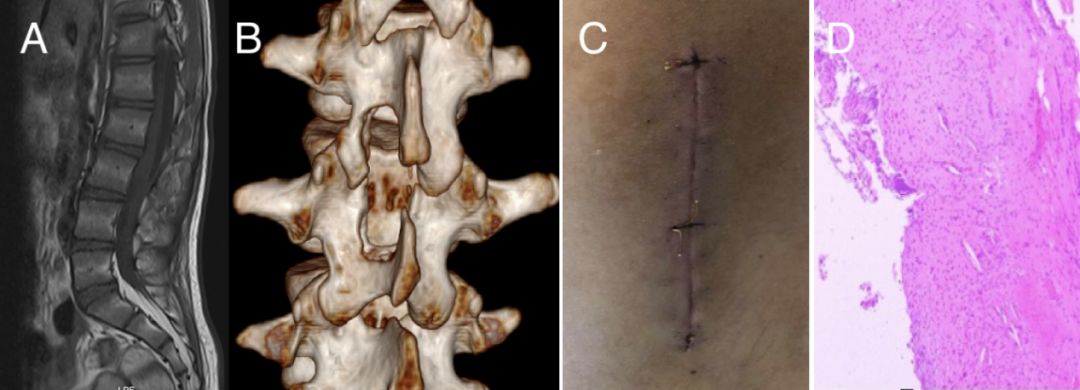

术后疼痛症状好转,复查MRI示肿瘤全切。脊柱CT三维重建显示上下椎板完整性保持良好(图3A,B)。

图3. A:术后复查MRI T1序列, B:术后CT重建骨窗, C:切口约8cm,皮内缝合, D:术后病理镜下组织。

病理回报:(L2-3椎管内肿瘤)良性囊性病变,内衬复层鳞状上皮,囊腔内及囊壁含胆固醇结晶及泡沫样组织细胞聚集,多核巨细胞浸润,囊壁可见骨组织。结合临床,符合畸胎瘤(图3D)。